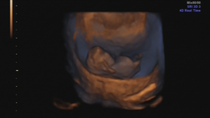

whoknew28 · 25/03/2015 21:09

So... here are the photos! The fancy 4D one is so weird - can't believe they can get such a defined pic at 10 weeks?! How was this baby only the size of a poppy seed 6 weeks ago? Mind. Blown.

Oh wow whoknew they are incredible pics!

Thanks Nonny and Batfish, even the sonographer was surprised by how good they were! Baby was just in the right spot, and it was a nice private clinic with brand new equipment, so all made for a clear pic.